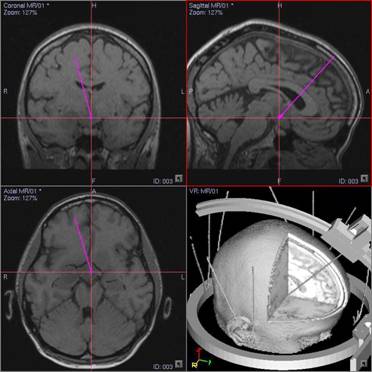

На базе Уральского межтерриториального нейрохирургического центра 31 больному с супратенториальными внутримозговыми опухолями головного мозга разнообразной гистологической структуры (глиальные опухоли различной степени злокачественности, метастатические опухоли) была проведена брахитерапия, как один из этапов комбинированного лечения. При опухолях, располагающихся в труднодоступных и функционально значимых областях головного мозга, для имплантации интрастатов использовали стереотаксический метод. Планирование предстоящей стереотаксической биопсии опухоли и траектории установки интрастата по магнитно – резонансным томограммам, а также по их 3D реконструкциям выполняли на навигационной станции «Stryker» (Leibinger). После установки и фиксирования интрастатов все пациенты транспортировались в отделение брахитерапии для проведения лечения. Расчёт дозы и поля облучения производили на планирующей системе «Abacus». Облучение проводили на аппарате GammaMed + с источником Ir192 (HDR). Объём клинической мишени (CTV) включал в себя зону контрастного усиления (по КТ) + 0,5 см к периферии. В режиме LDR (перманентная имплантация) к мишени доставляли дозу 40-60Гр за 5-10 дней. В режиме HDR (remote afterloading) использовали различные схемы фракционирования дозы 3-3,5-4-5 Гр за фракцию один раз в день или дважды в день с интервалом 6-8 часов. Суммарные дозы достигали 24-35Гр, что соответствовало длительности курса 3-5 дней. После достижения планируемой радиационной дозы интрастаты удалялись.

Описываем клинический случай стереотаксической брахитерапии, выполненной в Уральском межтерриториальном нейрохирургическом центре (ГБУЗ СО Свердловский областной онкологический диспансер), пациентке К. 31 год с глиальной опухолью диэнцефальной области (дна III желудочка). Данные МРТ головного мозга представлены на слайдах.

Этапы стереотаксической брахитерапии представлены на слайдах ниже.

2. Планирование траектории доступа для стереотаксической биопсии и для установки гибкого интрастата производилось на стереотаксической планирующей системе Stryker Leibinger по МРт и КТ реконструкциям, в том числе и в режиме 3D. Траектория из премоторного доступа в правом полушарии, проходящая через отверстие Монро в геометрический центр опухоли.